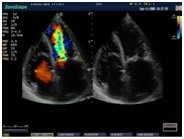

• многостороннее исследование сердца, при помощи специального набора кардиологических функций;

• исследования артериальных и венозных сосудов практически в любой области тела, при помощи 7 различных режимов допплерографии сосудов;

• расширенное цветовое допплеровское картирование;

• автоматический сегментный анализ движения миокарда;

• тканевой допплер;

• CW допплер на линейных датчиках;

• режим замедленной перемотки для тщательного исследования работы сердца;

- Кардиология